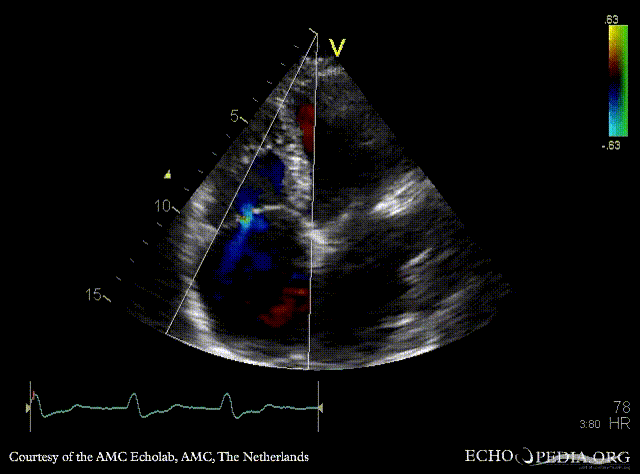

A4CH: diameter of dilated coronary sinus PSAX: dilated coronary sinus